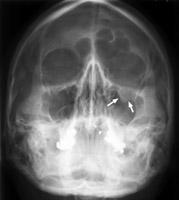

Tear Drop Sign (Orbits)

Blowout fracture

The floor of the orbit is the most common portion of the orbit to sustain fracture. A classic radiographic finding in blow-out fractures is the presence of a polypoid mass (the tear-drop) protruding from the floor of the orbit into the maxillary antrum The tear-drop represents the herniated orbital contents, periorbital fat and inferior rectus muscle.